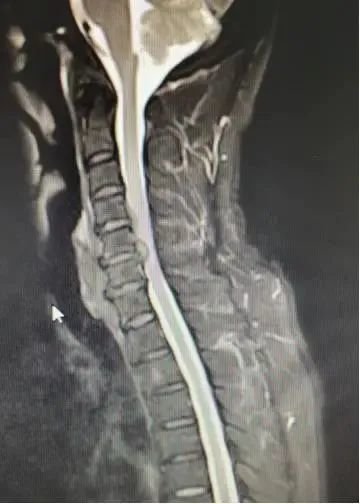

患者入院后完善相关检查,陈芳田主任详细查看病人情况后表示:患者颈椎间盘突出(C4/5、C5/6),颈椎椎管狭窄(C5/6),出现脊髓及神经压迫症状,诊断明确,非手术治疗效果不佳,患者手术指征明确,无明显手术禁忌症,可考虑予以手术治疗。

△患者术前影像学资料